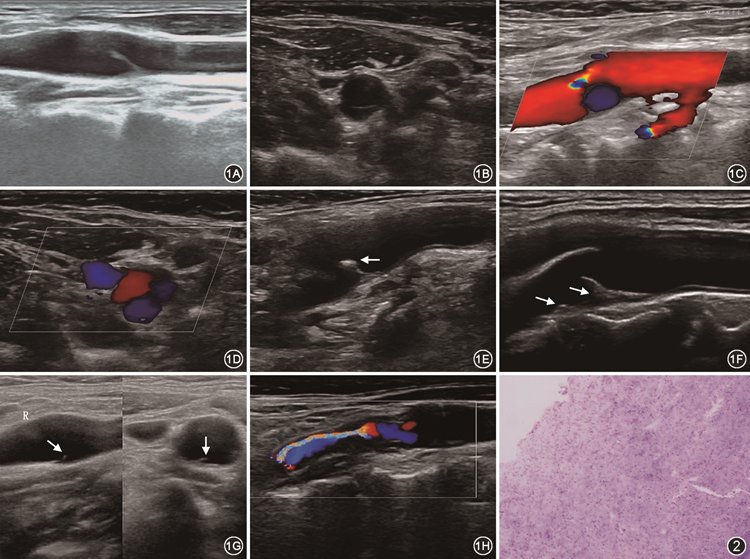

2. 颈动脉蹼的超声检查结果(图1):超声共检出32例颈动脉蹼。CD组中颈动脉蹼长度(4.88±1.60)mm,厚度(1.00±0.35)mm,与血管壁的夹角(46.58±11.14)°。超声所检出的颈动脉蹼均位于颈动脉后壁,其中14例(43.75%)位于左侧,其余位于右侧(56.25%);位于颈内动脉起始处后壁2例(6.25%),其余位于颈总动脉分叉处后壁(93.75%)。超声检测颈动脉蹼表面有斑块者1例(3.13%,图1E),颈动脉蹼底部合并有斑块者3例(9.38%,图1F)。

3. 超声与CTA诊断的比较:超声与CTA均正确诊断24例,超声与CTA均漏诊9例,超声正确诊断而CTA漏诊者8例,超声误诊而CTA正确诊断者1例。超声诊断颈动脉蹼的准确率高于CTA正确诊断率(76.19%比 59.52%,P=0.039)。超声与CTA诊断一致性比较的Kappa值为0.524,说明两种检查的一致性一般(P<0.001)。8例超声诊断为颈动脉蹼而CTA漏诊的病例,表现为长度2.7~3.3 mm、厚度0.4~0.6 mm的较短且纤细的颈动脉蹼(图1G)。

4. MD组与CD组的比较:MD组中,其中1例超声误诊为颈动脉夹层,后经CTA诊断为颈动脉蹼。其余MD组的病例均是颈动脉斑块所致局部血管重度狭窄或闭塞,后经手术病理证实均为颈动脉蹼周围粥样硬化斑块形成(图1H、图2)。MD组和CD组的颈动脉蹼局部情况及颈动脉其他部位情况的比较结果见表2。